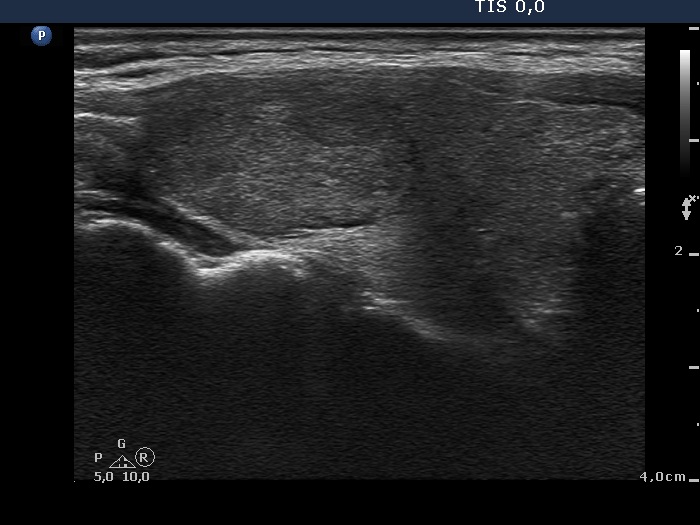

Ultrasonography. There was a moderately hypoechogenic nodule presenting halo sign and perinodular blood flow in the right while two smaller lesions in the left lobe. One of the latter displayed multiple microcalcifications.

The mass in the left side of the neck corresponded to a conglomerate of multiple lymph nodes. These were irregular in shape and presented cystic and necrotic areas. There was no hilum present. The lymph nodes were avascular.